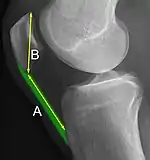

Patella baja.[4]

A patella baja is a low-riding patella. A long-standing patella baja may result in extensor dysfunction.[5]

Insall-Salvati ratio (A divided by B).[6]

The Insall-Salvati ratio helps to indicate patella baja on lateral X-rays, and is calculated as the patellar tendon length divided by the patellar bone length. An Insall-Salvati ratio of < 0.8 indicates patella baja.[6]